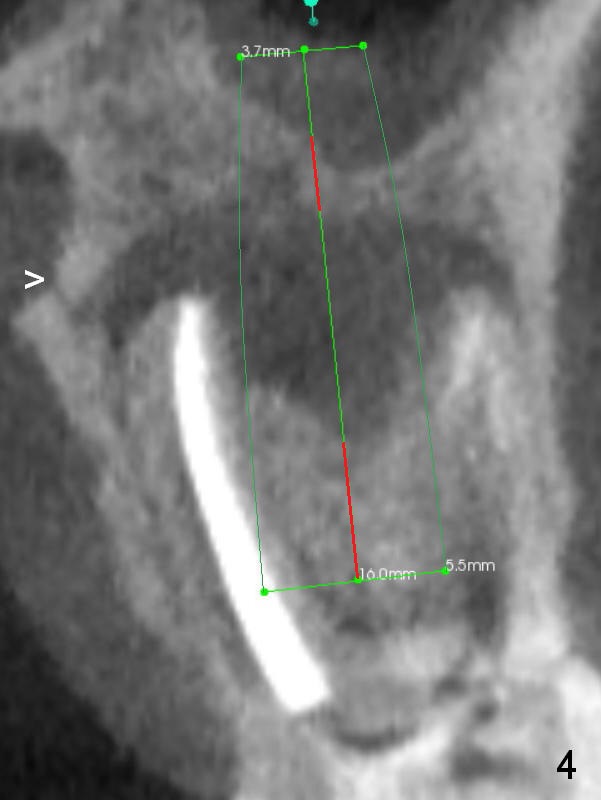

A 34-year-old man has persistent large periradicular radiolucency (Fig.1) after root canal therapy with a fistula (Fig.2). It appears that immediately after extraction (no Antibiotic) a long implant (15 or 16 mm, green outline) should be placed to bypass the bony defect with 2-point fixation (septum and sinus floor; Fig.3 (CBCT sagittal section), 4 (coronal section) red line). A shorter implant, which is placed at the septum (4-5 mm tall), is not expected to be stable. The diameter of the implant is to be determined after sequential osteotomy. The minimal will be 4 mm (Fig.5 axial section) as long as the implant or osteotomy does not perforate the palatal (P) or buccal (B) socket substantially. The bone density at the septum and the sinus floor is 1100 and 200-400 units, respectively. Drills and osteotomes (Tatum or Magic Expanders) will be used for osteotomy in these 2 segments, respectively.